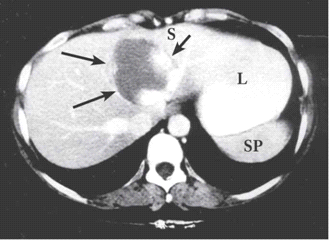

בטומוגרפיה ממוחשבת ניתן לראות מילוי של חומר ניגוד בהמנגיומה (תצלומים 15.10-17.10).